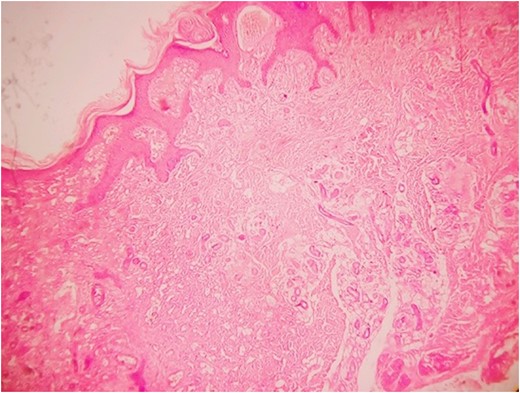

Histopathology examination revealed grayish white to grayish brown lesions with hyperkeratitis of the epidermis and focally hyperplastic stratified squamous epithelium. Papillary dermis with numerous dilated, thin walled congested capillaries and the deep dermis with increased number of eccrine glands and numerous capillary channels intermingled with eccrine structure. The stroma was composed of fibrofatty tissue along with few pilar structures with the focal distribution of granulation tissue. Such a histological picture was found to be consistent with a diagnosis of EAKH.

A 1.5-year-old girl child presented with multiple painless, flesh-colored lesions (total 3 in number) over the posterior aspect of her right leg since birth. The lesions have gradually progressed in size to attain the present size of 4 × 3 cm2 (largest one) with central ulcers. It was accompanied crusting. Other similar lesions without ulcer of the size 3 × 1 cm2 and 1.5 × 1 cm2 were present superiorly. All the lesions were of irregular shape and had well-defined demarcation from normal skin. No one else among her immediate family had the similar lesion. Doppler report of the lesion ruled out any increased vascularity thus ruling out the suspicion of a haemangioma. FNAC also pointed out towards a hamartomatous lesion and advocated for a detailed examination for confirmation. The lesion was surgically excised and was submitted for histopathological examination (Figs 1–4).